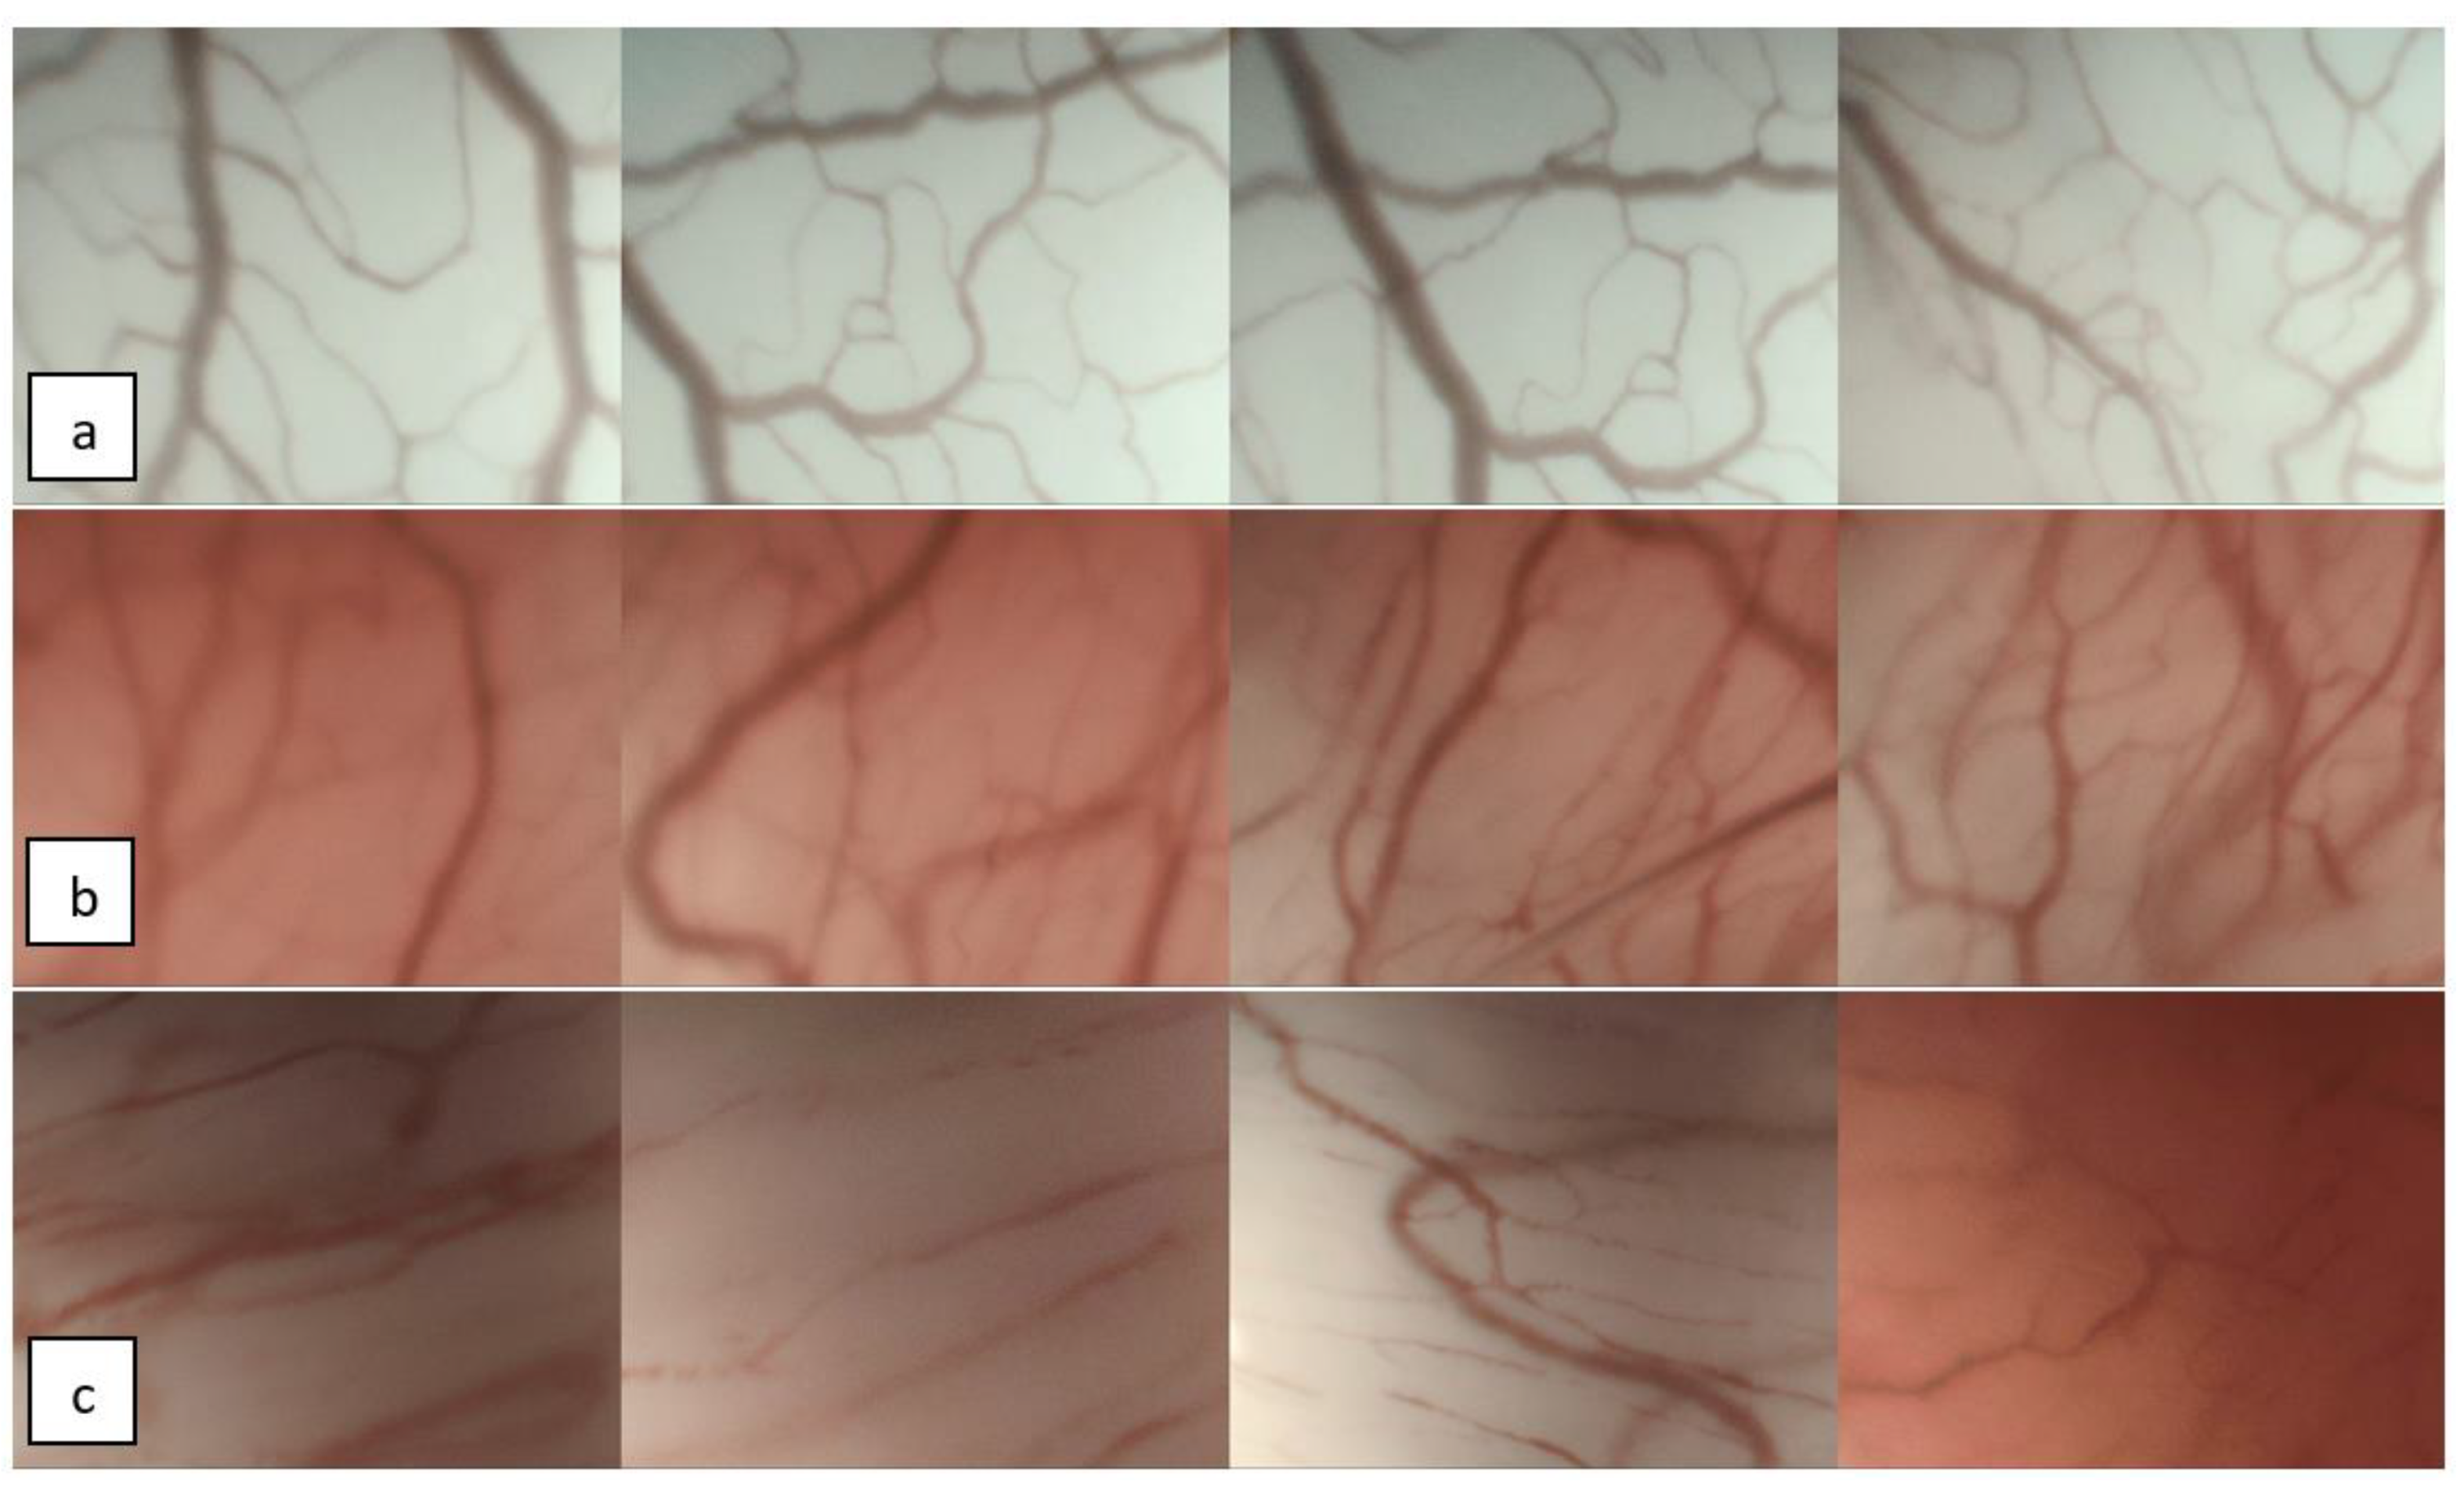

4.1. Endoscopic Evaluation of Vascular Patterns of the Vocal Folds

4.2. ELS Classification for Vascular Changes of the Vocal Folds